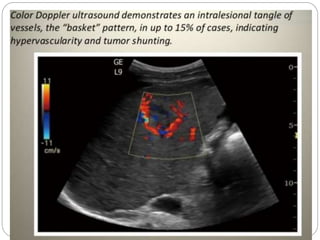

USG  USG -vary  Small HCC’s (<3cms) -> hypoechoic with posterior acoustic enhancement ( fatty change/ marked sinusoidal dilatation)  >3cms- mosaic or mixed pattern  May invade poratl vein  CD:central vascularity

 USG - vary

 Small HCC’s (<3cms) ->

hypoechoic with posterior

acoustic enhancement ( fatty

change/ marked sinusoidal

dilatation)

 >3cms- mosaic or mixed pattern

 May invade poratl vein

 CD:central vascularity